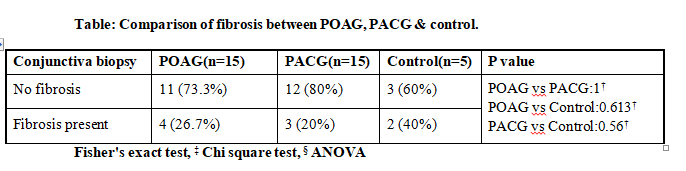

Histopathological pattern evaluation is shown in table:

The comparison of POAG & PACG group respectively with control group as well as with each other was not statistically significant.